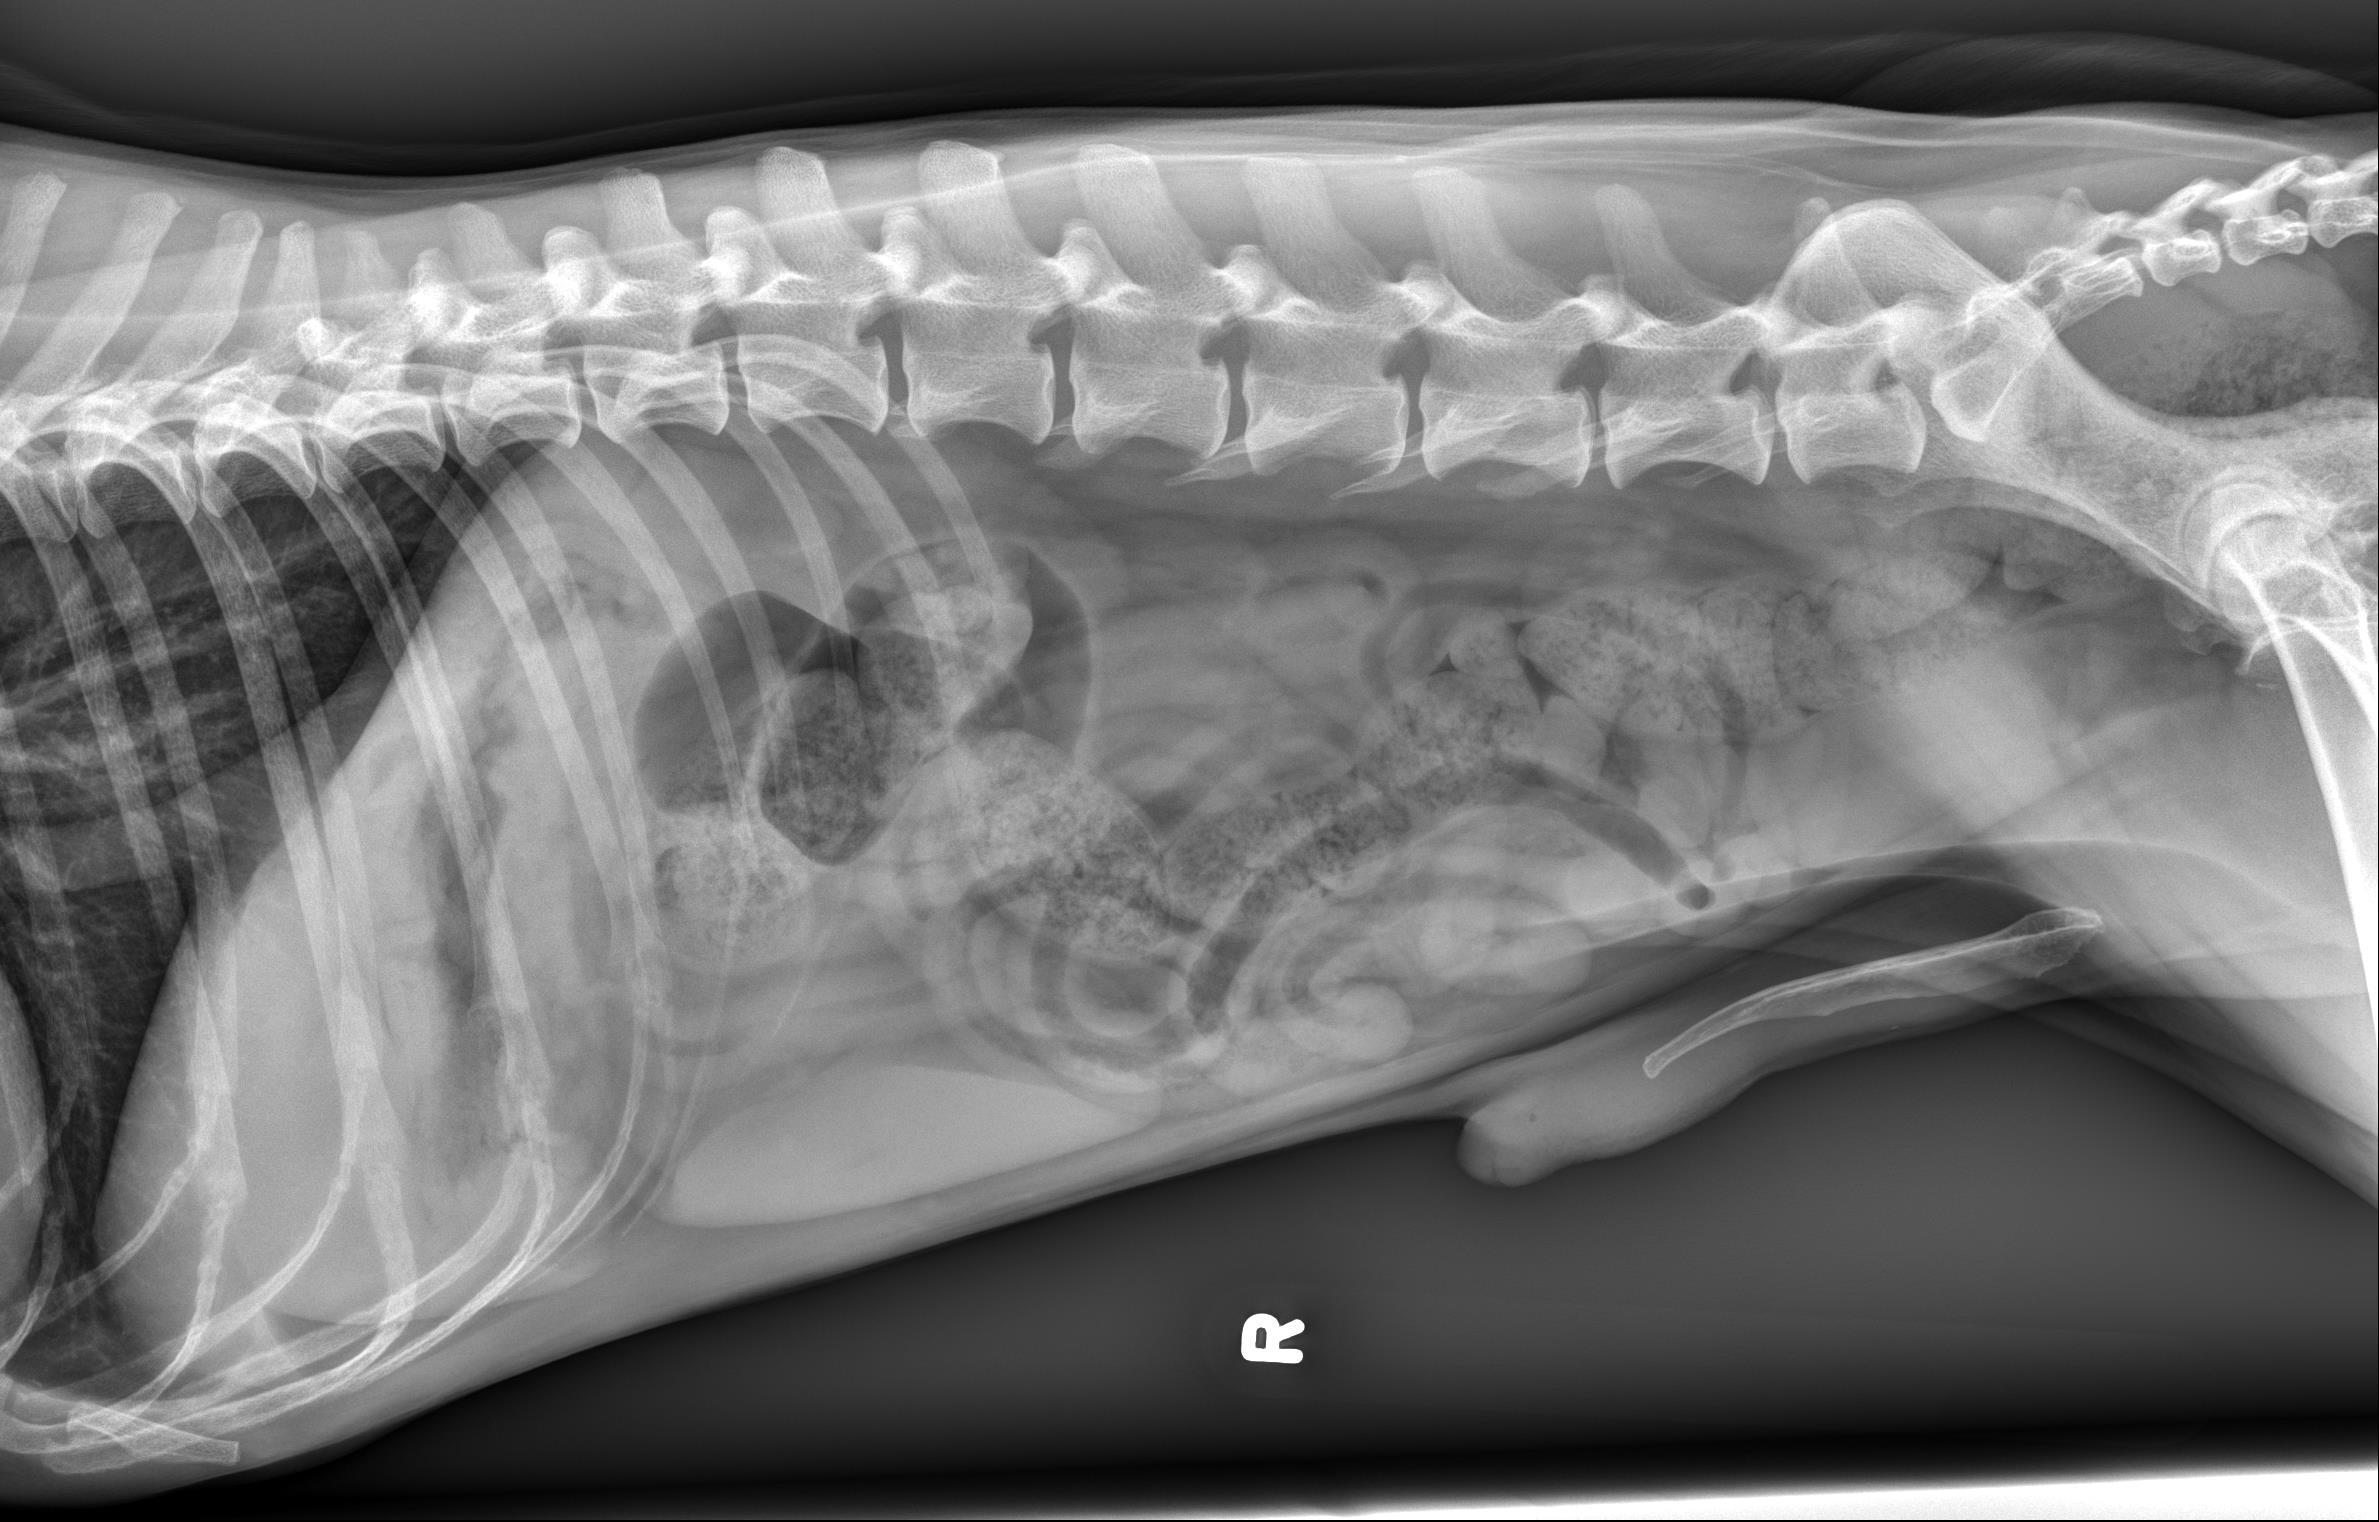

10 year old male castrated dog. History of chronic hematochezia for the last 3 months.

Orthogonal radiographs of the abdomen are available for interpretation.

Abdominal serosal detail is normal. The liver is small which results in cranial deviation of the gastric axis. Otherwise, the gastrointestinal tract, spleen, kidneys and urinary bladder remain normal. The included portions of the thorax remain normal.

The size of the liver likely represents a normal patient variant, however, an underlying chronic hepatopathy cannot be entirely excluded. A cause for the patient’s reported hematochezia is not identified on the current radiographic study.